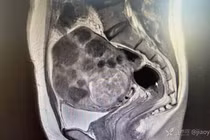

Trì hoãn việc này, bệnh nhân 42 tuổi tử cung “mọc” u chi chít như sung

(Kiến Thức) - Phát hiện u xơ tử cung cách đây 5 năm, bệnh nhân 42 tuổi không hề điều trị. Chủ quan suốt thời gian dài đến khi bụng to bất thường, người phụ nữ đi khám rồi ngỡ ngàng phát hiện tử cung “mọc” u chi chít như sung.

Trang Sohu đưa tin, bệnh nhân 42 tuổi có tử cung “mọc” u chi chít như sung sống tại Trung Quốc. Người phụ nữ nhập viện trong tình trạng bụng phình to, không đau, không ra máu âm đạo hay tiết dịch bất thường. Ngoại trừ sự thay đổi vùng bụng, cô không chóng mặt, mệt mỏi, khó chịu hay hồi hộp. Chu kỳ kinh nguyệt khá ổn định. Mỗi kỳ kinh kéo dài 5-6 ngày, khoảng cách giữa các đợt chừng 24 ngày.

Được biết, bệnh nhân phát hiện u xơ tử cung cách đây 5 năm. Thời điểm đó, cơ thể không có biểu hiện khó chịu nên cô trì hoãn việc điều trị.